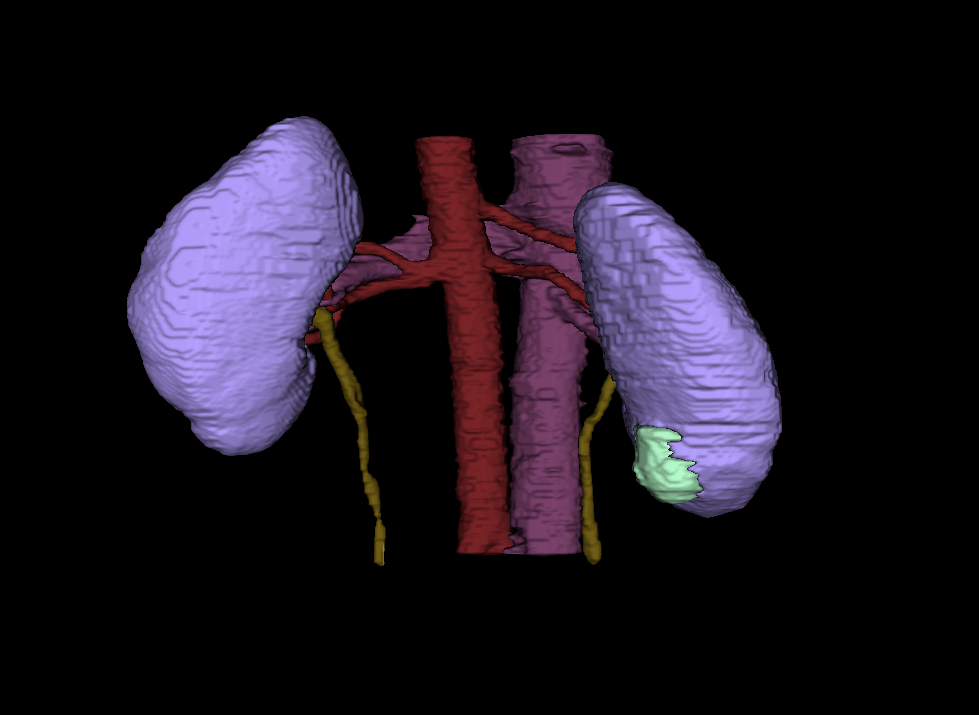

Heller is a PhD student conducting computer science research at University of Minnesota. His research focuses on using computer technology to enhance medical imaging, like a CT scan or an MRI. According to Heller, the magnified images will allow radiologists to quantify the type of tumor it is, saving time between a patient’s diagnoses and treatment.

“They will be able to measure a tumor mass, determine how big and rough they are, and whether they look distinct or blurry against the background. Medical professionals can use that information to choose the most effective treatment and predict a patient's outcome,” Heller explains.

“Then we can turn those numbers into a computer code. If we can automate the code with images and equipment, a radiologist can just hit a button and receive information on the tumor, rather than looking at the image and making a judgement call,” Heller states.

Eventually, Heller hopes using data driven decisions will create useful tools for radiologists and aid in the discovery of visual biomarkers for non-invasive kidney cancer. Most importantly, the computer algorithms would help medical professionals become more effective in treating the disease and allow scientists to conduct more research based off the numerical patterns they see in each stage of the disease.

In 2019, Heller’s team organized a competition and released their vast data collection on kidney tumors to the public. Known as the Medical Image Computing and Computer-Assisted Intervention (MICCAI) Kidney Tumor Segmentation Challenge, or “KiTS, Heller asked participants to design and train their own machine learning algorithm models using the data and parameters given to them. As it turns out, the UMN group’s segmented kidney cancer dataset was the first of its kind to be used in this type of competition—and drew a lot of interest in the medical community. “We had more than 100 teams from around the world participate in the challenge,” he says. “The event was held in conjunction with a conference in China, so there was a lot of international collaboration. It was a great experience.”